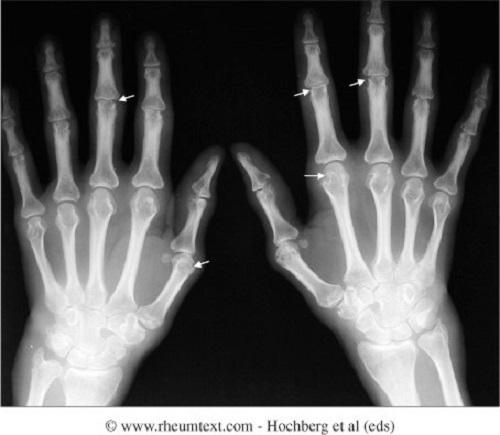

Ουρική αρθρίτιδα

Πρόκειται για μια ρευματική νόσο που εισβάλει πολλές φορές θορυβοδώς με έντονο πόνο στις αρθρώσεις πρήξιμο ερυθρότητα και μερικές φορές χαμηλό πυρετό. Τα ενοχλήματα αυτά…